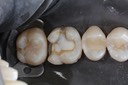

Mark Chun #13 pre-op

Mark Chun #13 composite removal